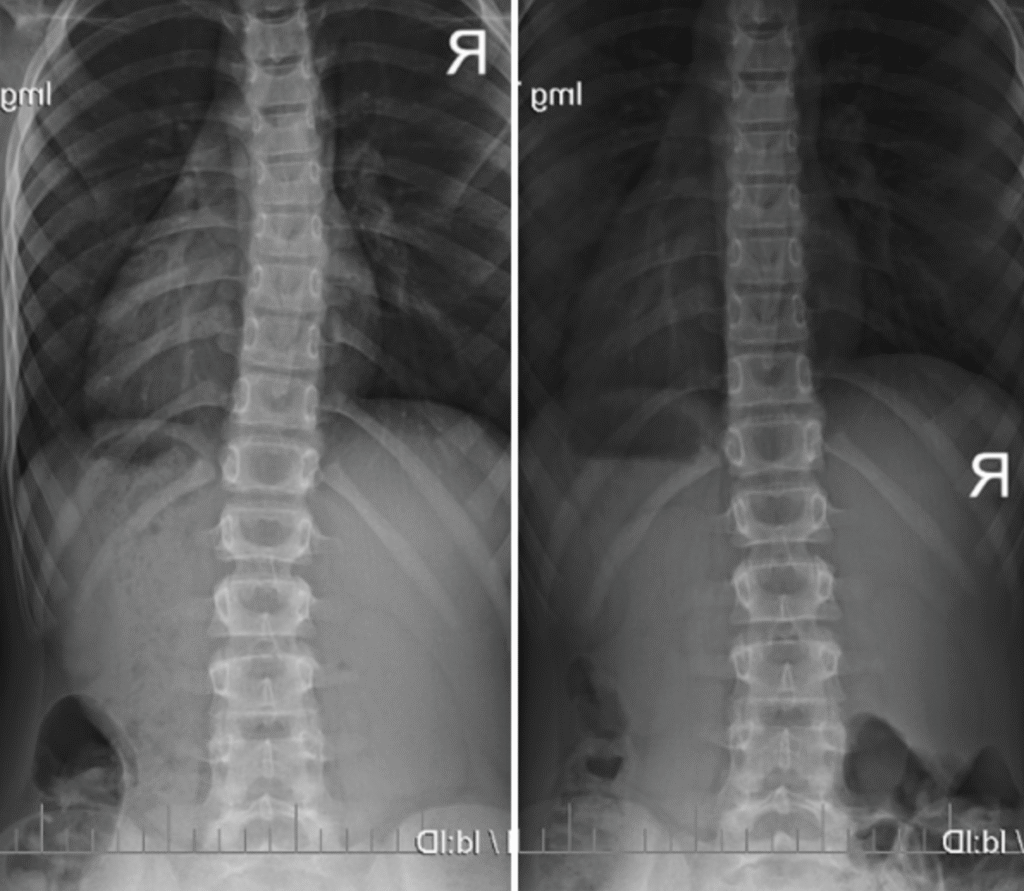

Piotr – 10 lat

Terapia prowadzona w okresie 15.09 – 01.12.2008 (20 zabiegów) Częstotliwość zajęć – 2 x tydz.